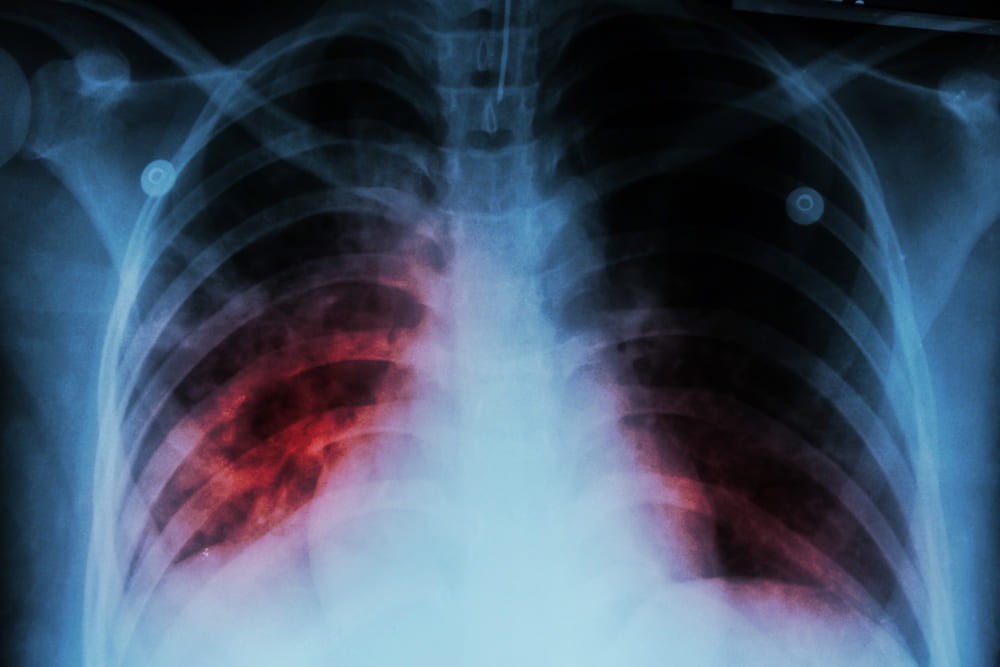

แร่ใยหินอันตราย เพราะร่างกายไม่สามารถกำจัดออกได้ เส้นใยจะฝังลึกในปอดและสะสมระยะยาว นำไปสู่โรคปอดใยหิน (Asbestosis) มะเร็งปอด และมะเร็งเยื่อหุ้มปอด โดยอาการมักแสดงหลังได้รับฝุ่นเข้าไปแล้วประมาณ 10-20 ปี